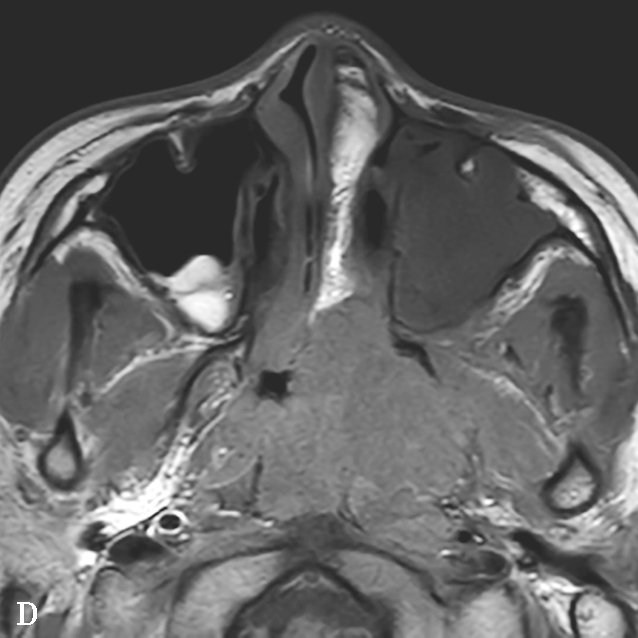

图1-2-4 青少年鼻咽纤维血管瘤

患者男,12岁,间断鼻出血1年。A.鼻窦CT横断面骨窗,示左侧蝶腭孔扩大,被不规则软组织肿块占据,病变累及左侧鼻腔、鼻咽、翼腭窝,邻近骨质可见溶骨性骨质破坏;B.鼻窦CT冠状面重组骨窗,示病变累及鼻腔、蝶窦,邻近骨质可见溶骨性骨质破坏;C.鼻咽部MR T 2 WI横断面,示左侧鼻咽、鼻腔不均匀等信号肿块,病变通过扩大蝶腭孔累及翼腭窝,病变内可见多发血管流空信号;D.鼻咽部MR T 1 WI横断面,示病变呈不均匀低信号;E.鼻咽部MR T 1 WI横断面增强+脂肪抑制序列横断面,示病变显著不均匀信号,与邻近组织分界尚清